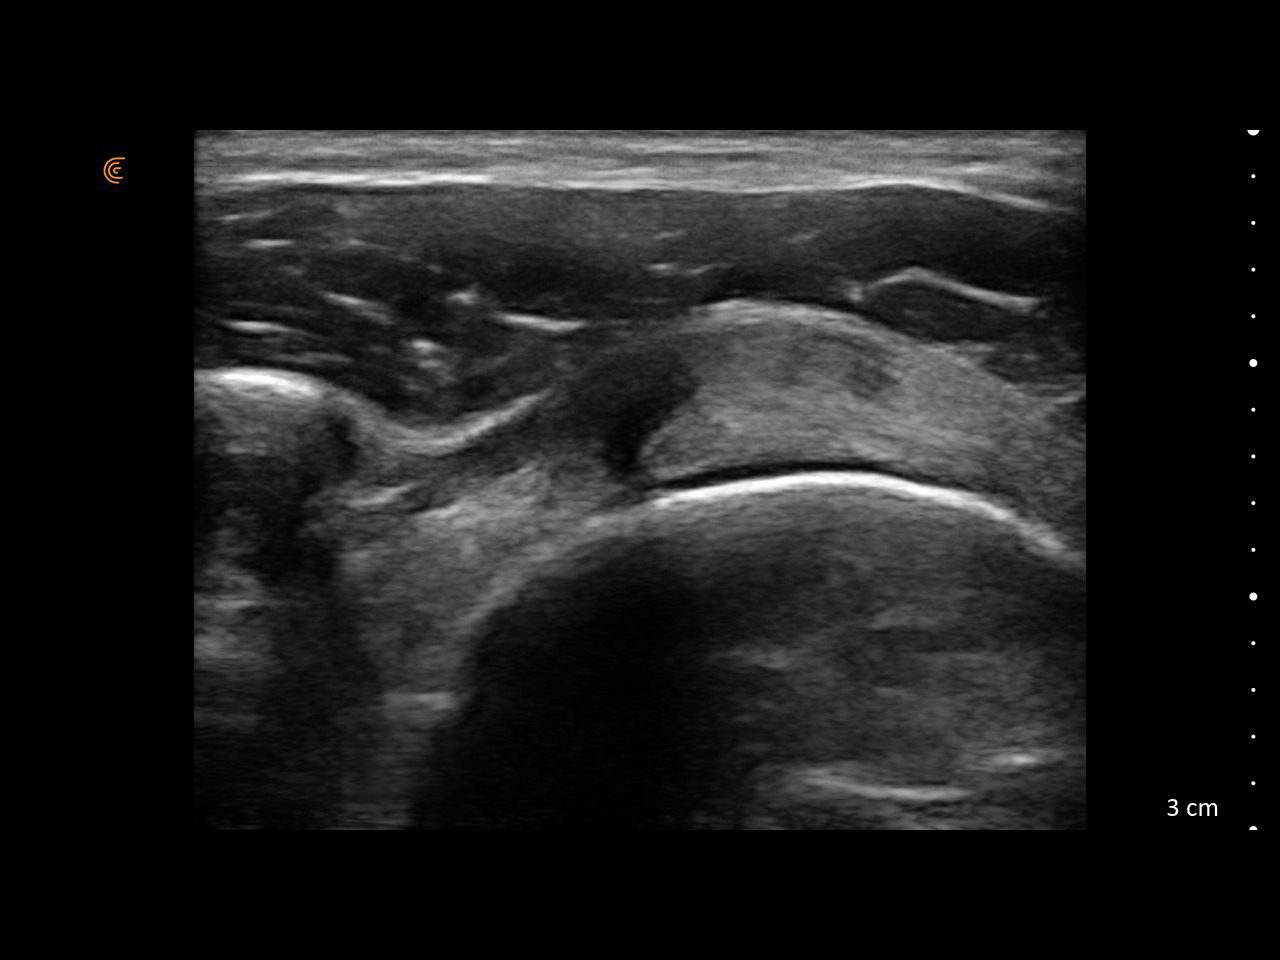

Visualize targets in real time to deliver PRP or cortisone—even in complex joints. Instantly diagnose sprains, tears, and effusions, and make confident decisions about surgical intervention

Assess synovitis, enthesitis, and monitor treatment efficacy with high-resolution ultrasound, enabling precise, real-time joint and soft tissue evaluation, accurate needle guidance, and improved confidence in clinical decision-making.